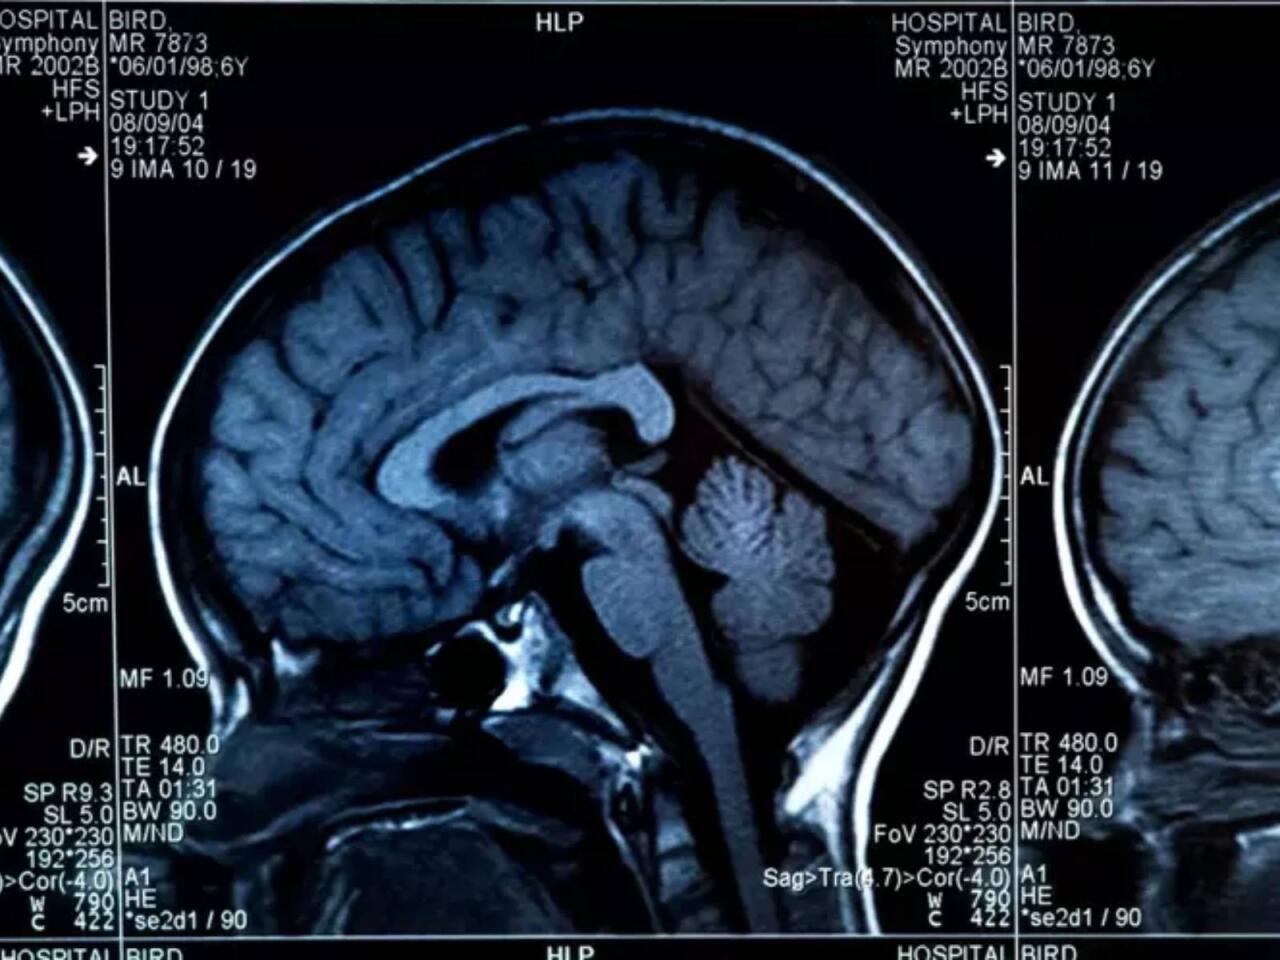

Beynin sağlamlığını təhlükəyə atan 8 qida açıqlanıb.

Milli.Az xəbər verir ki, aşağıdakı qidaların çoxluğu beynin sürətini zəiflədir.